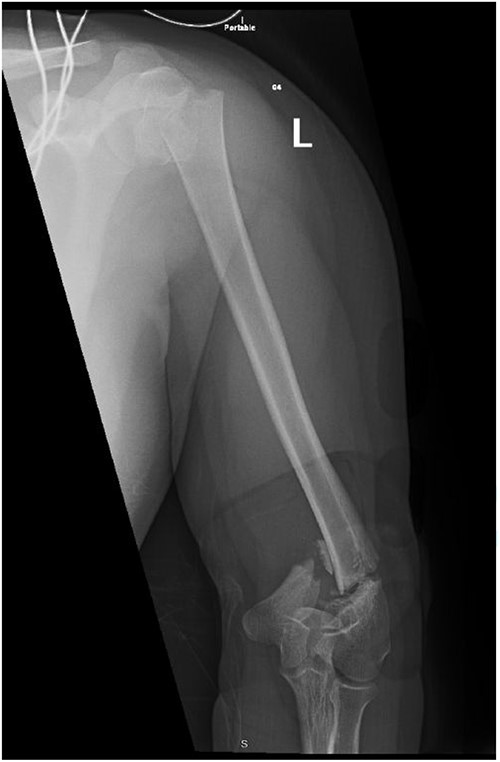

Upon arrival the patient underwent exploratory laparotomy followed by irrigation and debridement of both femur and humerus and application of external fixators (Fig. 2). The patient was admitted to the intensive care unit (ICU). Two days later, the patient underwent open reduction and internal fixation of both proximal and distal humerus (Fig. 3).

Anteroposterior (AP) view of the left humerus and elbow after ORIF.

The patient underwent left open reduction and internal fixation of proximal and distal humerus under general anesthesia. The patient was placed in the lateral position. Preparation and draping in the usual sterile manner were performed and a sterile tourniquet was used. The distal humerus was first approached through a posterior approach. Ulnar nerve protection and olecranon osteotomy was done, showing simple distal intraarticular fracture with minimal metaphyseal comminution. Anatomical reduction of the articular fracture was achieved, with preliminary fixation by k-wires holding the intra-articular fragments. This was followed by interfragmentary screw fixation from medial to lateral. Dual plate fixation (posterolateral and medial anatomical plates) was used to fix both medial and lateral columns, connecting the articular fragment to the metaphyseal. Reduction was confirmed under x-ray. Joint was tested for any screw penetration, and none was found. The osteotomized olecranon was reduced and fixed with cannulated screws and tension bands. The ulnar nerve was protected throughout the whole procedure and was reduced back into the cubital tunnel. Range of motion was examined; full range of motion was achieved. Finally, closure was done in layers.

The patient was then shifted from lateral to beach-chair position, and preparation and draping were repeated. A deltopectoral approach was utilized reaching to the proximal humerus. Reduction was achieved, followed by preliminary fixation with k-wires. Philos plates were used to fix the fracture. Range of motion was examined afterward, with no struggles detected. Fluoroscopic images were taken later to make sure no screws had penetrated the joint. Closure in layers was done, followed by dressing and application of an arm sling.